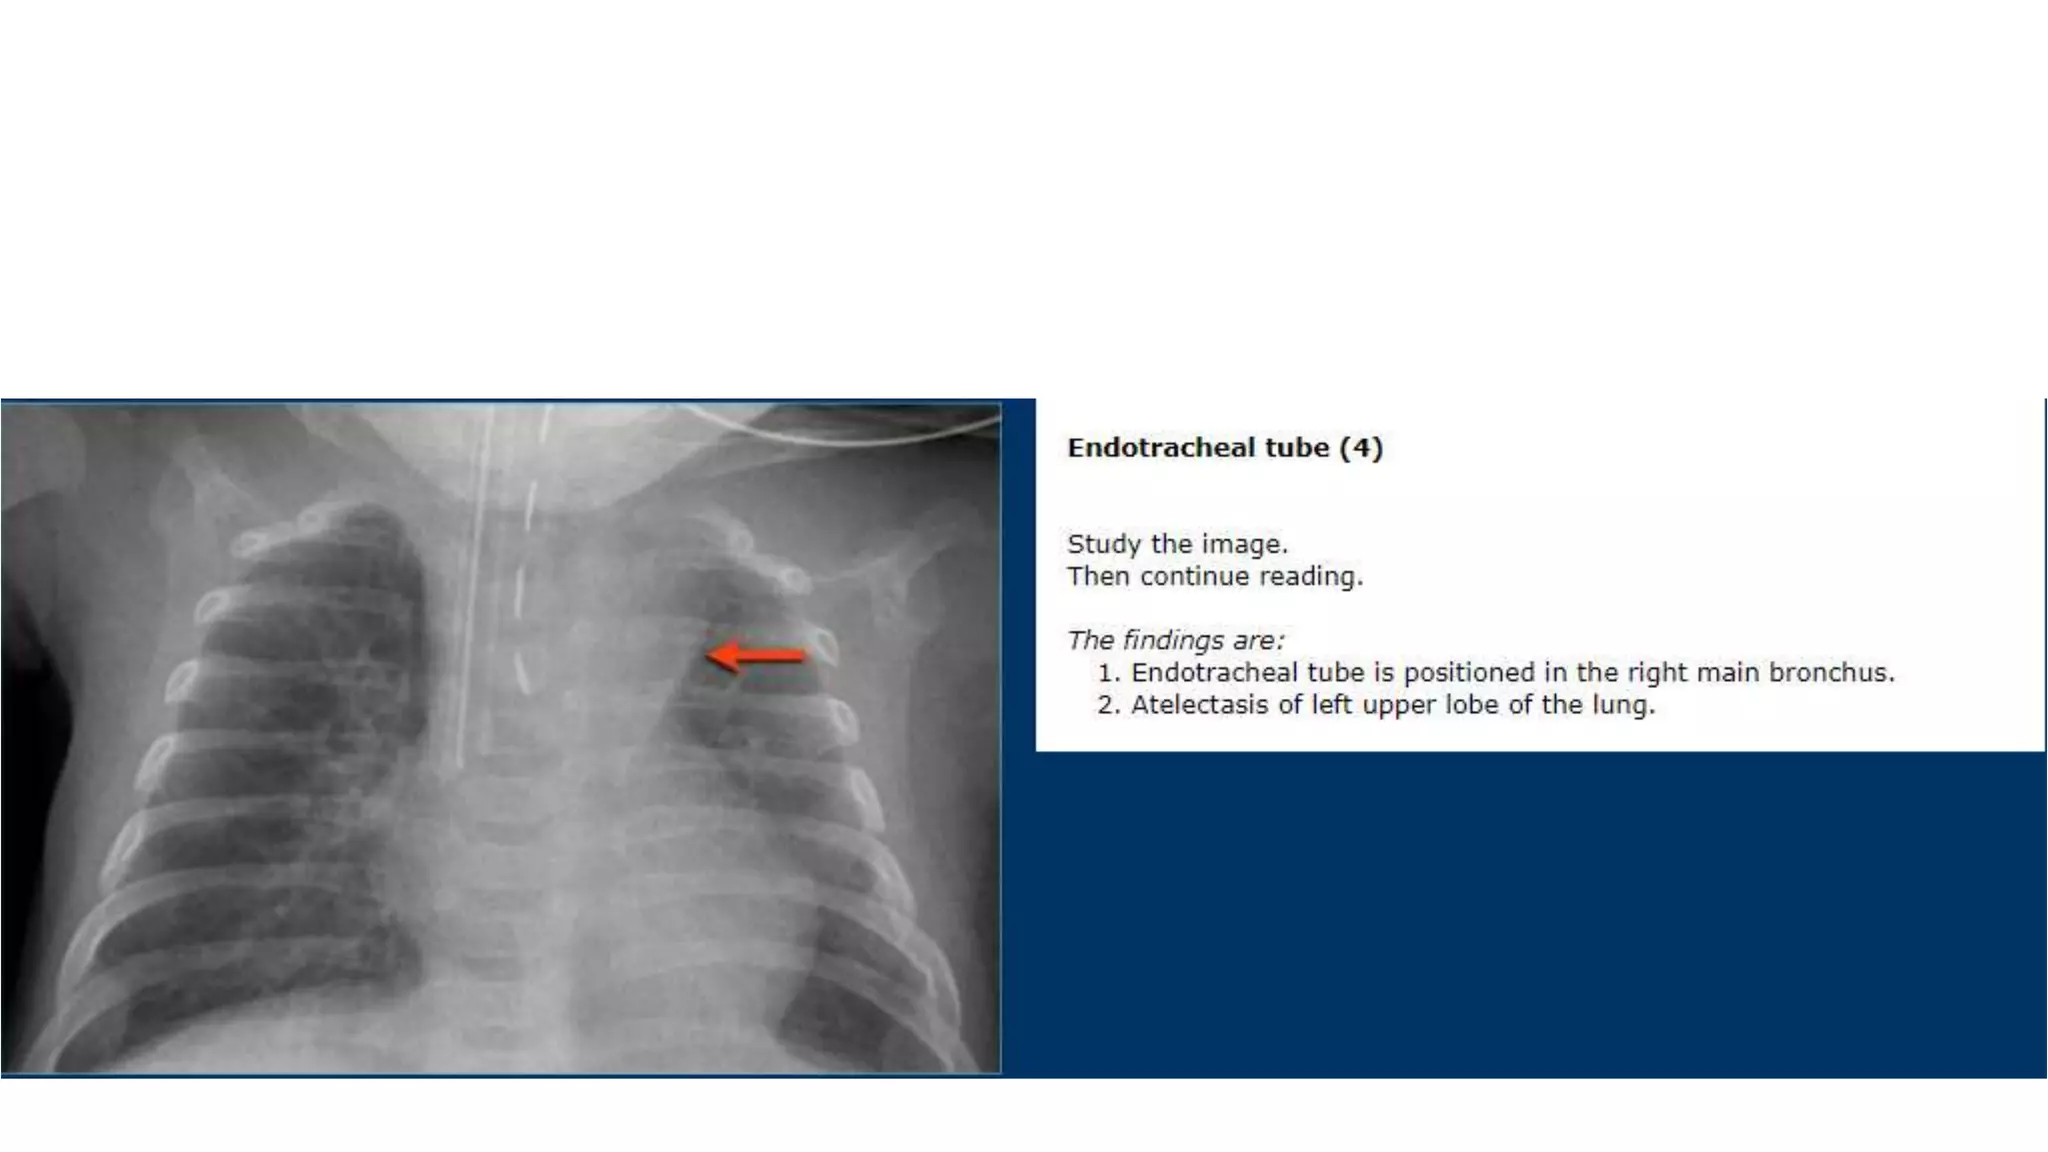

This document provides an overview of neonatal chest x-rays, including when they should and should not be performed, what a normal x-ray looks like, common positions of tubes and catheters, and common causes of respiratory distress in neonates. It discusses the appearance of a normal chest x-ray as well as conditions like respiratory distress syndrome, transient tachypnea of the newborn, meconium aspiration syndrome, and pneumonia. Surgical conditions like diaphragmatic hernia and esophageal atresia are also reviewed.